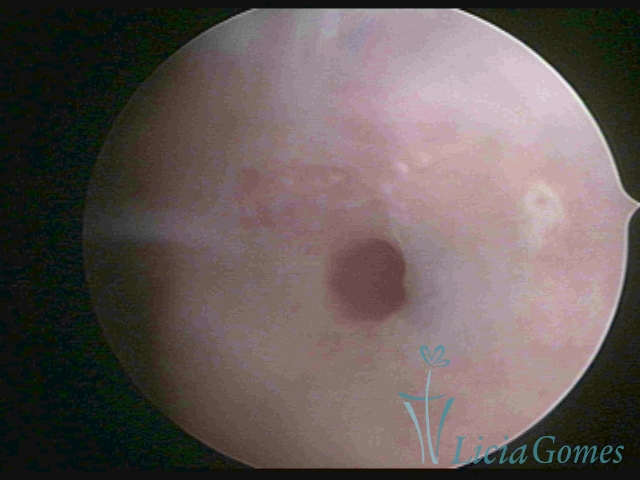

Third part or upper section

Presents the mucosa with a smooth, poorly vascularized surface, to the internal orifice